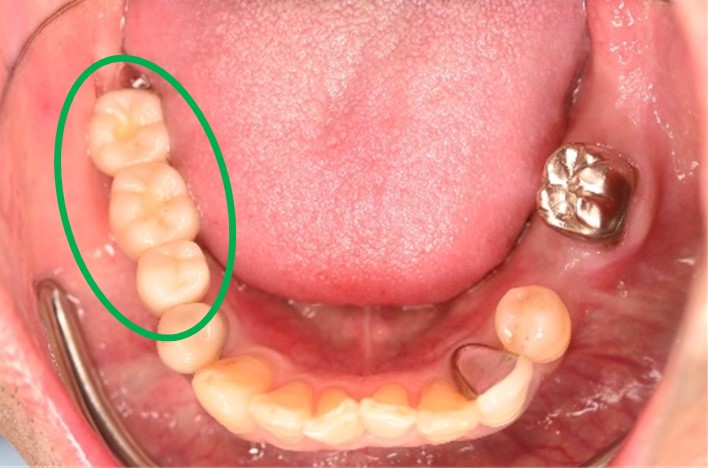

Before

▼初診時に使用していた部分入れ歯を装着したところ

▼インプラント埋入前

After

▼インプラント埋入後